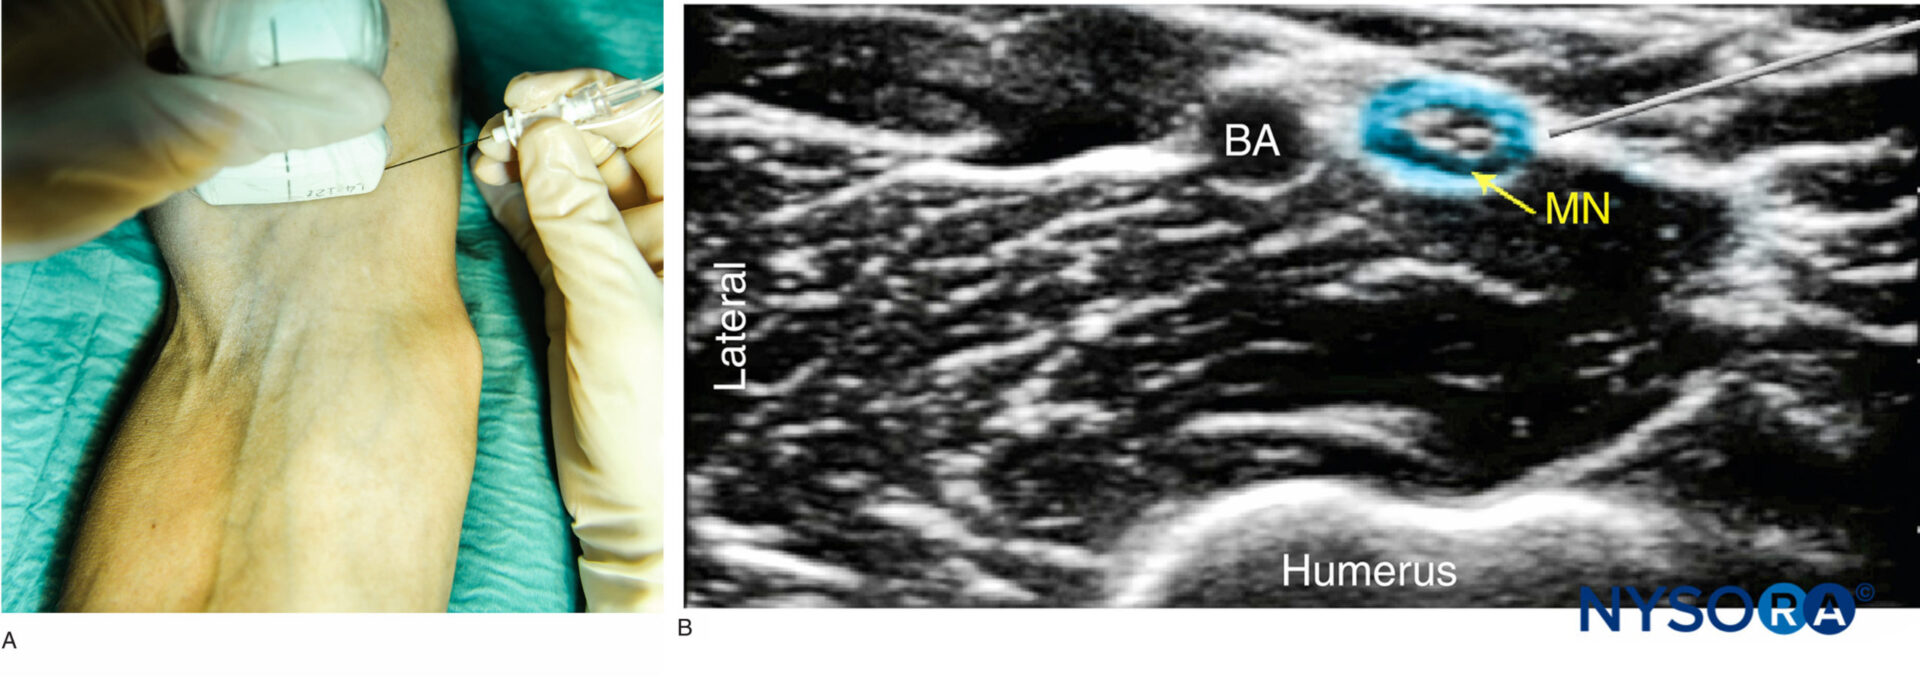

From www.nysora.com

regionalanesthesiapositionofarmprobeneedleformediannerveblock Nerve Block And Local Anesthetic a comprehensive textbook on peripheral nerve blocks for regional anesthesia practitioners, with detailed illustrations, anatomy, techniques, and. — identify the toxicokinetics of local anesthetics. — learn about the indications, benefits, and techniques of peripheral nerve blocks (pnbs) for surgical and. a nerve block is the injection of numbing medication (local anesthetic) near specific nerves to decrease. Nerve Block And Local Anesthetic.